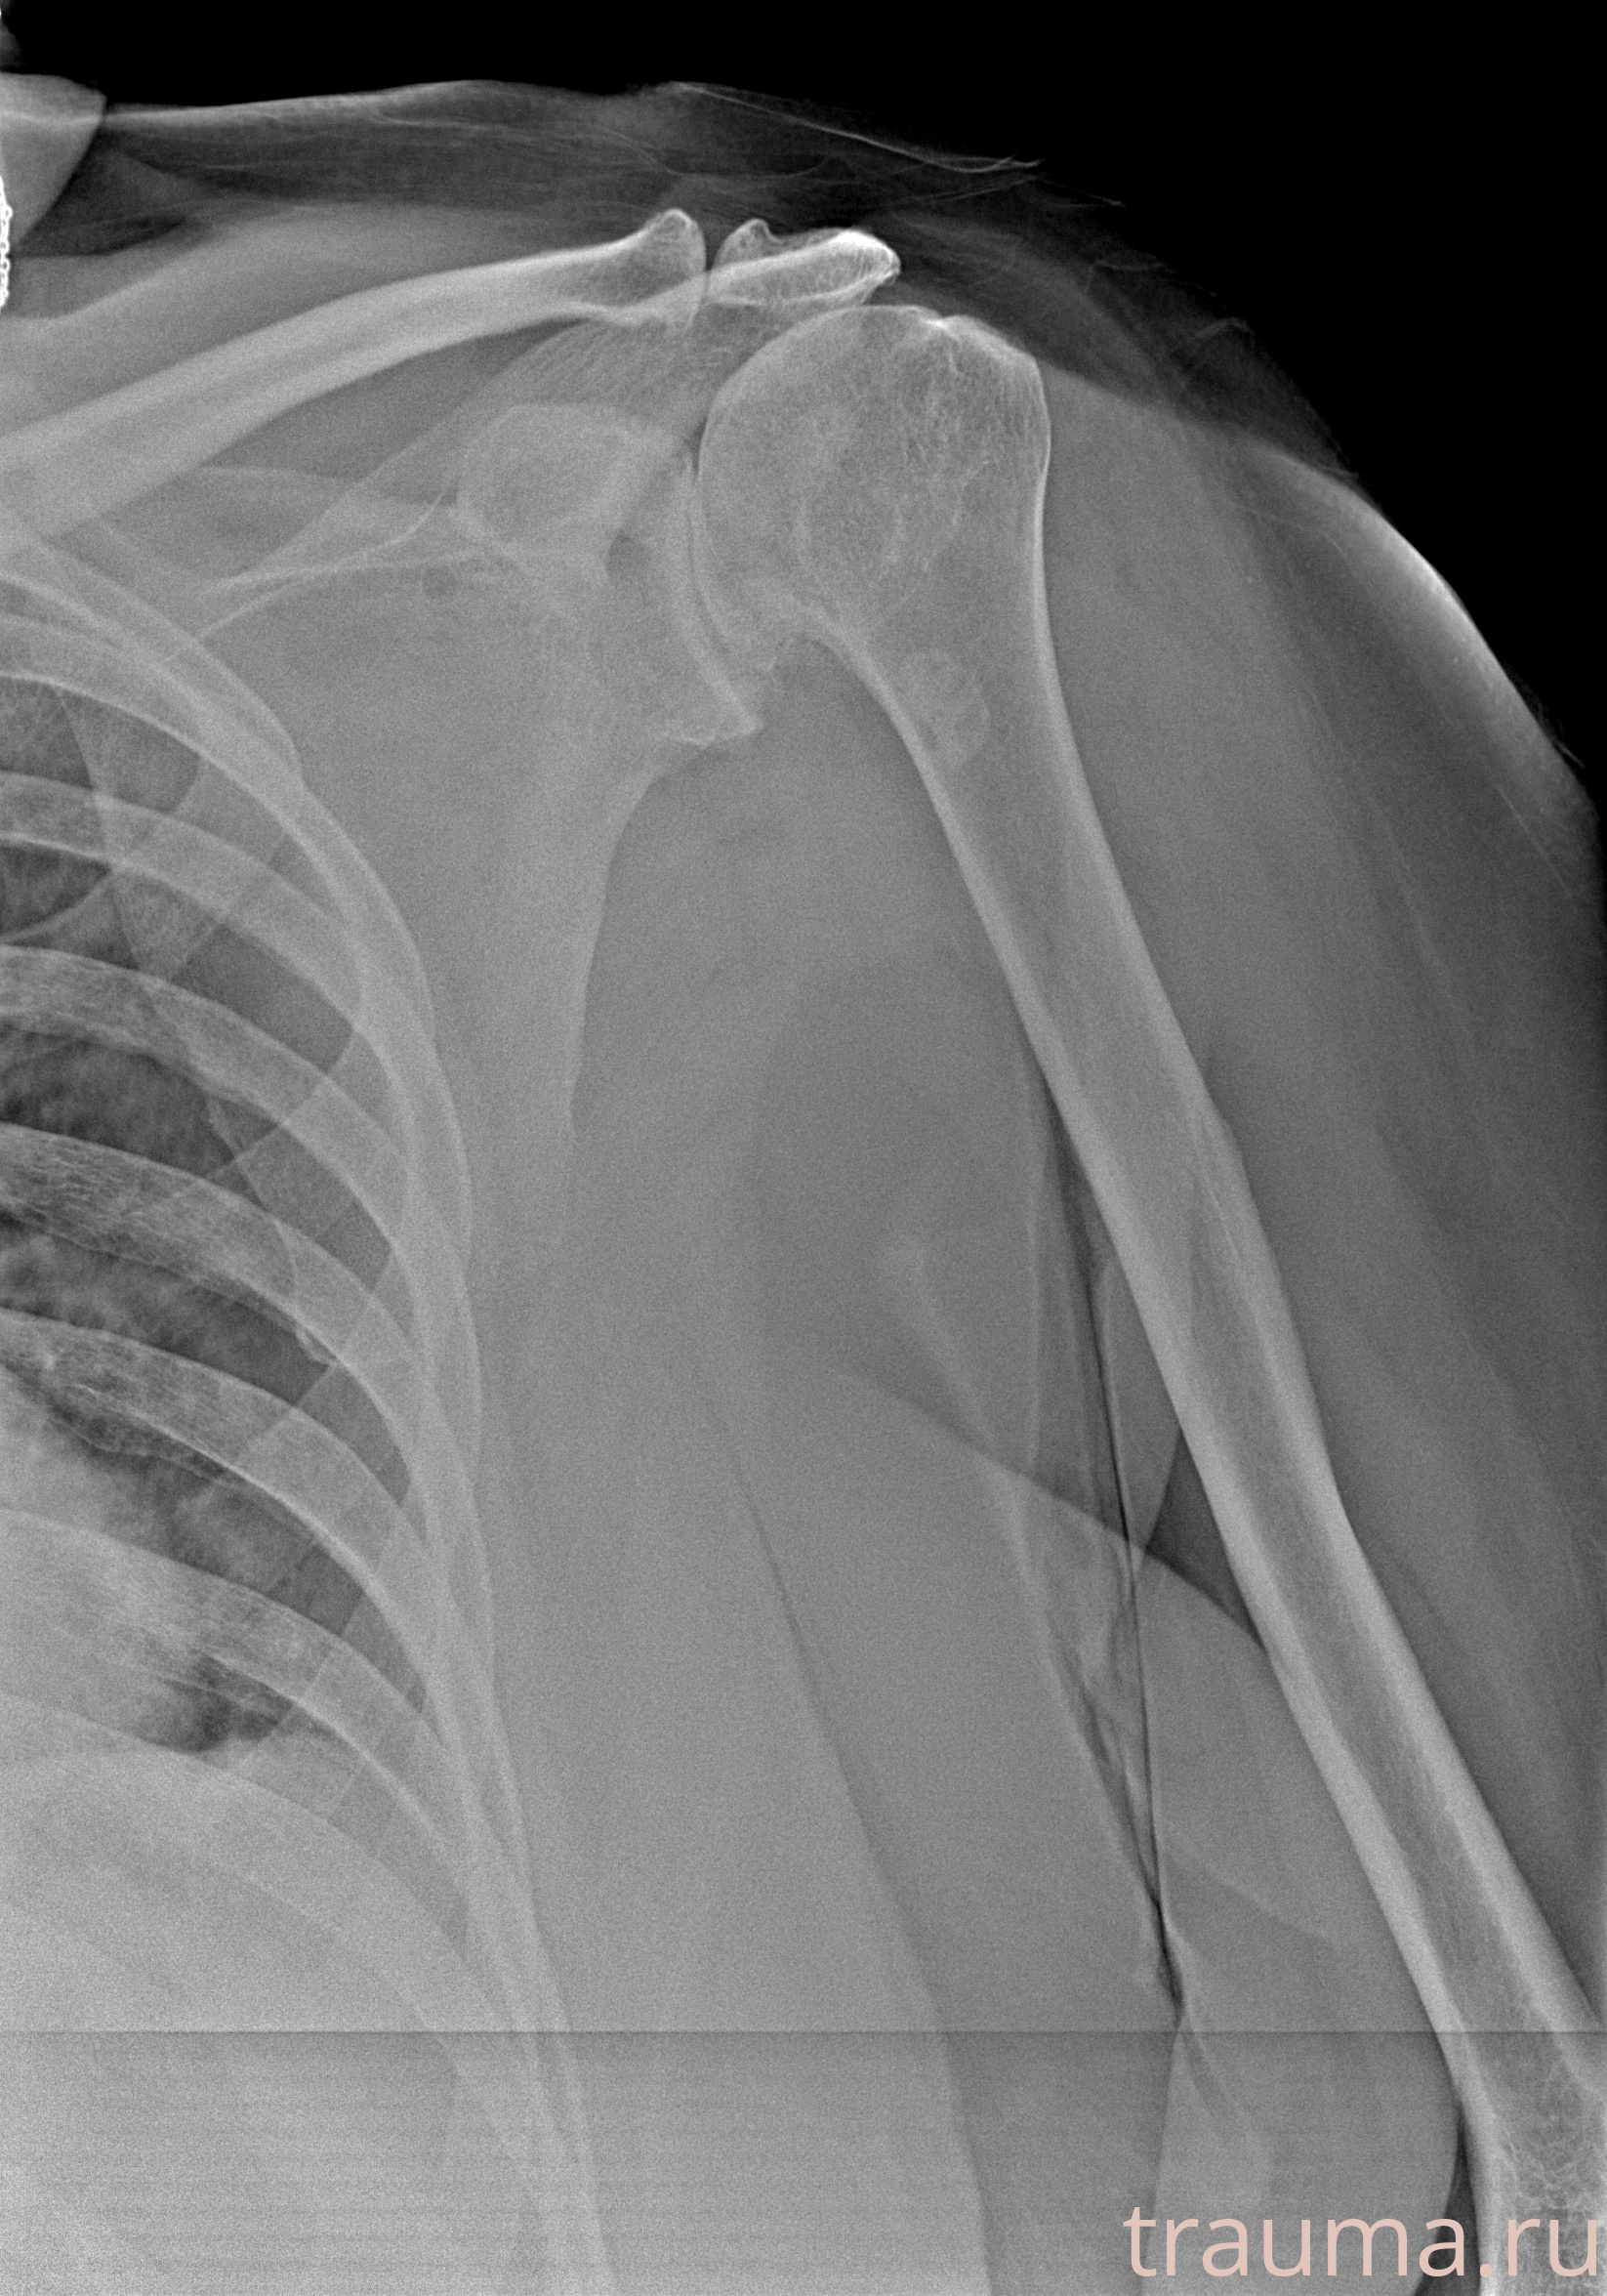

Рентгенограммы

Рентген на дому: по вашему адресу приезжает врач-рентгенолог, травматолог-ортопед с мобильным рентгеновским аппаратом, проводит диагностику травмы или заболевания, делает необходимые рентгенограммы, дает рекомендации по дальнейшему лечению. Получить качественные снимки в домашних условиях возможно благодаря уникальной методике, разработанной МосРентген Центром для института  Склифосовского